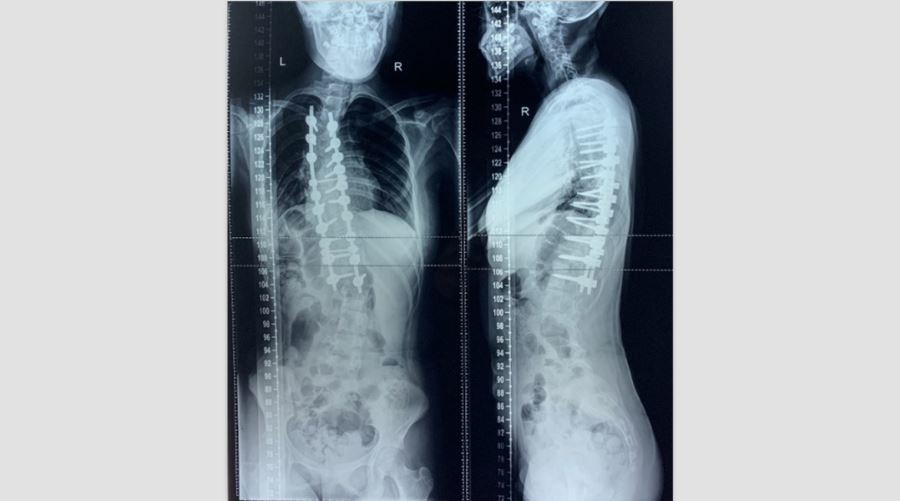

2018年01月患者入院术前X线片:胸部Cobb角71°,腰部Cobb角64°

2018年01月生长棒及多米诺滑块置入术2018年03月术后复查

2020年04月彻底根治矫形术胸部Cobb角50°,腰部Cobb角30°站高154cm,坐高122cm